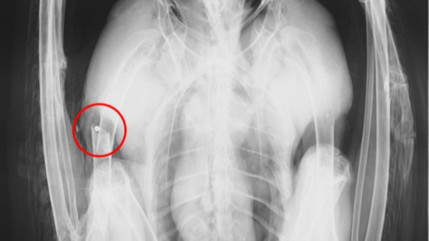

Il tire sur un aigle royal : la LPO porte plainte

Le 20 novembre dernier, le centre de soins pour la faune sauvage de l'Isère le Tichodrome a recueilli un aigle royal.